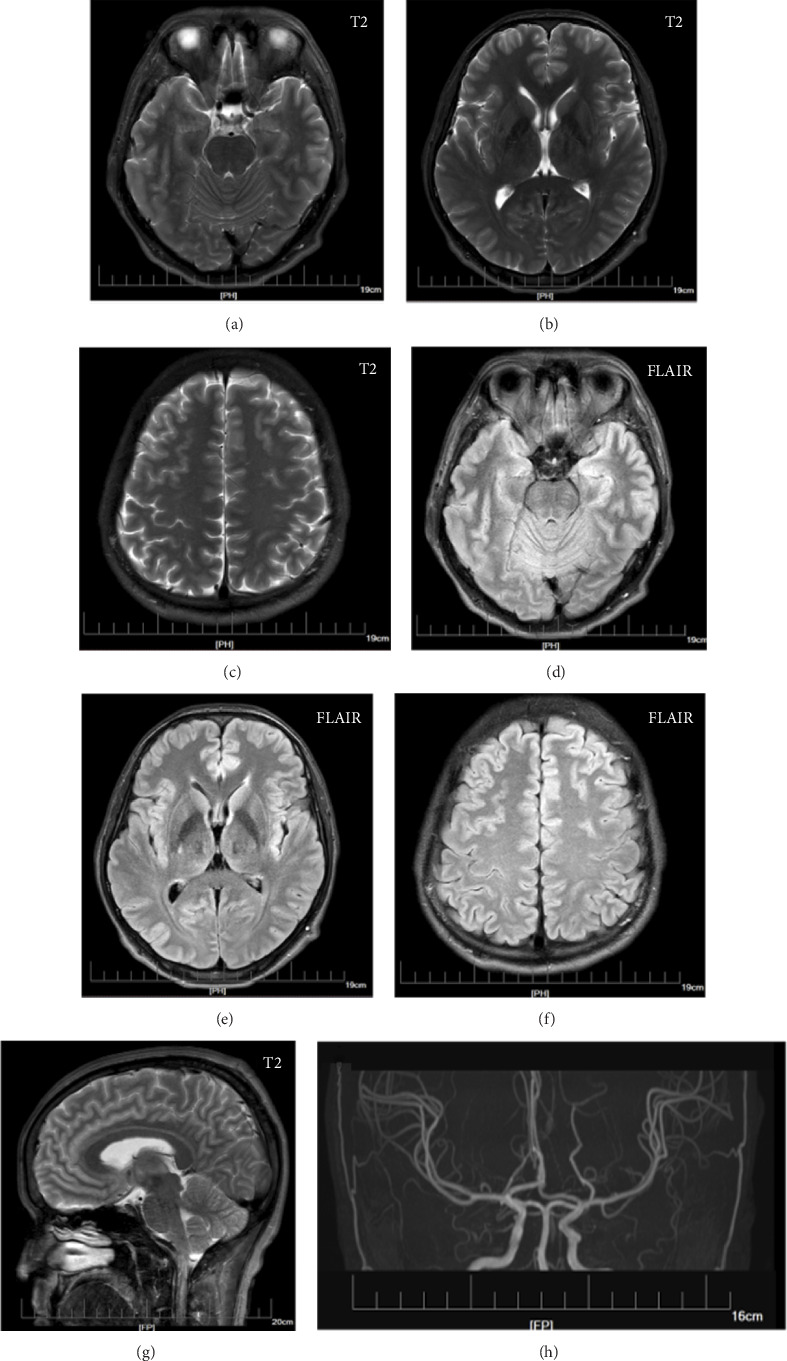

Phosphatase and tensin homolog (PTEN), a tumor suppressor gene, is also associated with neurological phenotypes, including macrocephaly, Cowden syndrome, and autism spectrum disorder. We present a 34-year-old Chinese male who complained of recurrent seizures within one year. His occipital frontal circumference was 62.8 cm. Whole-exon sequencing revealed that he carried a heterozygous missense mutation of NM_000314.4:c.4375C > T (p.Met35Val) in PTEN gene. Therefore, heterozygous mutations of c.103A > G in PTEN may increase the risk of macrocephaly with epilepsy.